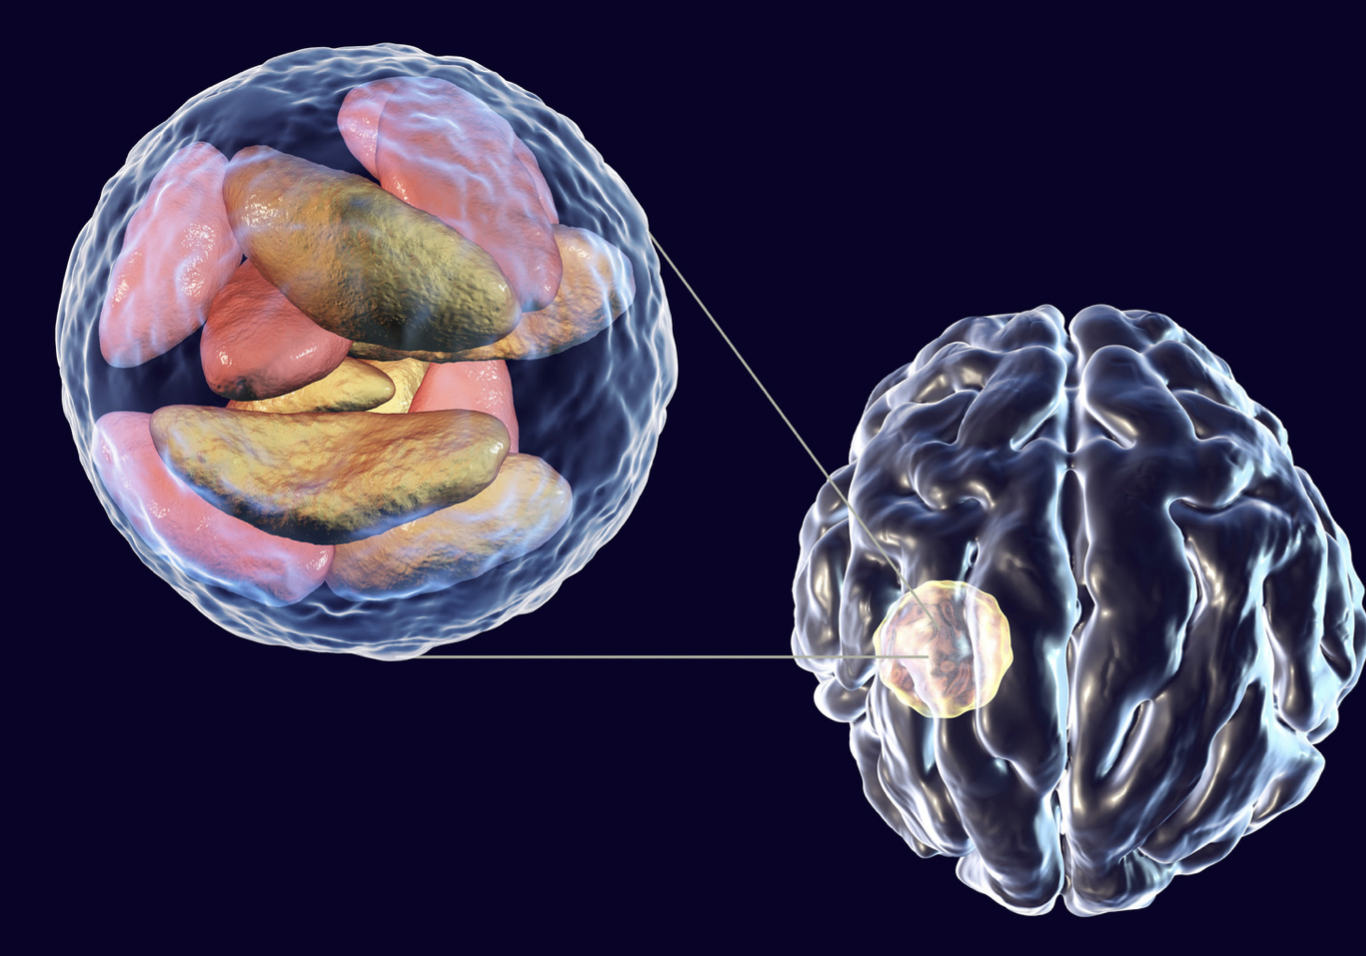

Meningitis adalah peradangan pada cairan dan lapisan meninges, yaitu lapisan yang menyelubungi otak serta sumsum tulang belakang (medula spinalis). Peradangan yang disebabkan oleh meningitis dapat menimbulkan gejala seperti nyeri kepala, demam, dan leher yang kaku. Insiden kasus meningitis di dunia bervariasi, mulai dari jumlah kasus yang lebih rendah pada Eropa dan Amerika (sekitar 1 kasus per 100.000 penduduk) hingga yang tinggi di Afrika (800 hingga 1000 kasus per 100.000 penduduk). Di Indonesia, terdapat 1,2 juta kasus meningitis bakteri terjadi setiap tahunnya. Angka kematian akibat kasus ini sekitar 135.000 jiwa.

Meningitis dapat disebabkan oleh virus, bakteri, jamur, dan parasit. Infeksi virus merupakan penyebab yang paling sering menyebabkan meningitis, diikuti oleh infeksi bakteri, jamur, dan parasit. Penyebab meningitis yang cukup banyak di Indonesia adalah bakteri Mycobacterium tuberculosis yang juga menyebabkan tuberkulosis (TB) paru. Berdasarkan laporan WHO, sekitar 1.020.000 orang menderita meningitis TB di Indonesia pada tahun 2015.

- Meningitis bakteri disebabkan oleh adanya bakteri dari situs infeksi di organ lain yang kemudian masuk ke pembuluh darah dan menembus sawar darah otak. Adanya bakteri menyebabkan lapisan meninges meradang. Pada beberapa kondisi, infeksi bakteri dapat secara langsung menyerang lapisan meninges. Hal ini disebabkan oleh infeksi yang lebih dekat dengan otak, seperti infeksi telinga atau sinus. Agen bakteri yang menyebabkan meningitis antara lain Streptococcus pneumoniae, Neisseria meningitidis, Mycobacterium tuberculosis, dan Haemophilus influenzae.